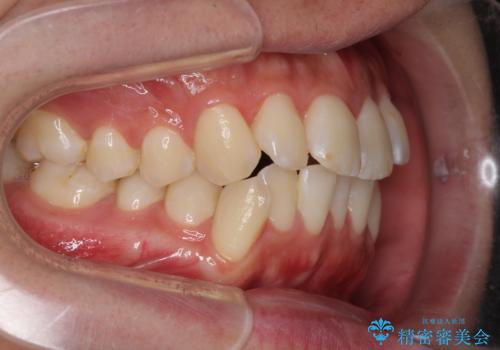

- 前歯のデコボコと若干口元が突出していることを気にして来院された患者様です。

全体的に軽微な叢生が認められ、口元もやや前方に突出していたため、インビザラインでのIPR(歯と歯の間を削る)と歯列全体の後方移動によって歯並びを整えることとしました。

上下ともに歯列の幅が狭かったため、側方に拡大することで前歯のデコボコや突出感を解消するためのスペースを獲得することができました。